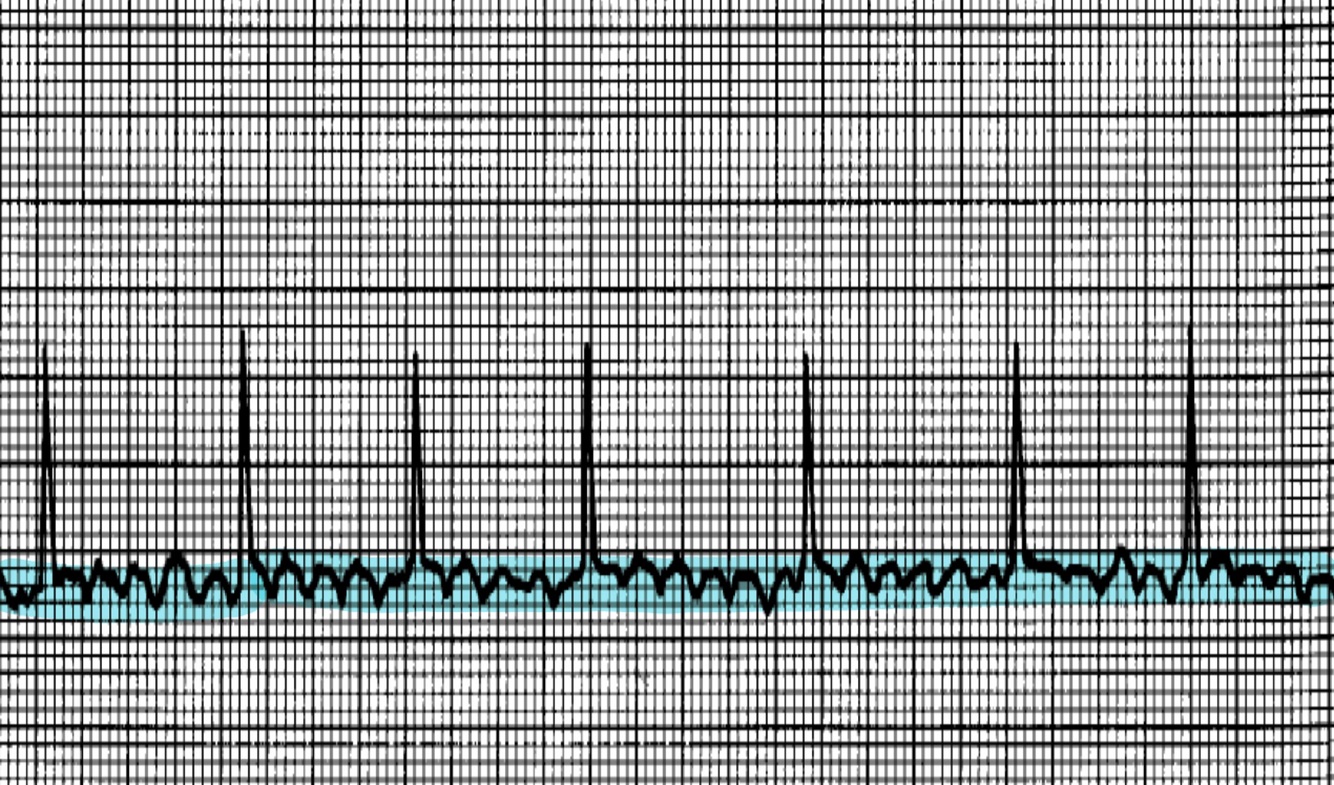

Name that rhythm

A

Premature Atrial Contraction (PAC)

Rate: underlying rhythm, irregular at PAC

Rhythm: irregular

P waves: one for every QRS, but PAC is different